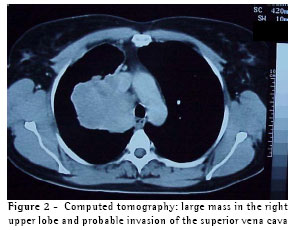

A computed tomography scan of the chest revealed atelectasis of the right

upper lobe (caused by occlusion of the upper lobe bronchus) that extended up to the juxtacarinal portion of the main bronchus, accompanied by infiltration of the wall of the main left bronchus, which resulted in invasion of the right branch of the pulmonary artery and of the arch of the azygos vein. There was no sign of invasion of the chest wall or of pleural effusion (Figure 2). Tomographic findings led us to suspect invasion of the superior vena cava and azygos vein. Therefore, we performed a cavography, which did not reveal any involvement of these structures (Figure 3).